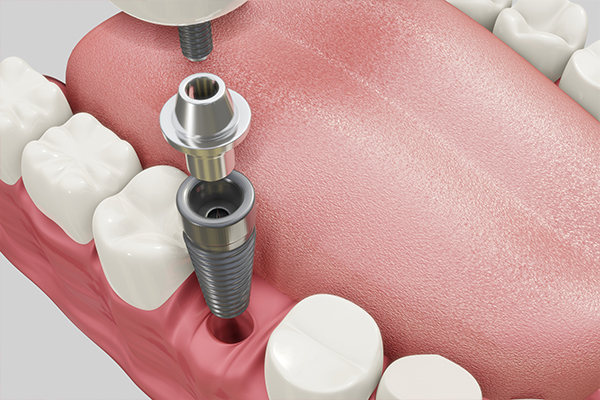

임플란트란?

치주질환이나 외상 등의 이유로 치아가 상실된 경우, 자연치아를 대체해주는 술식 중 하나입니다.